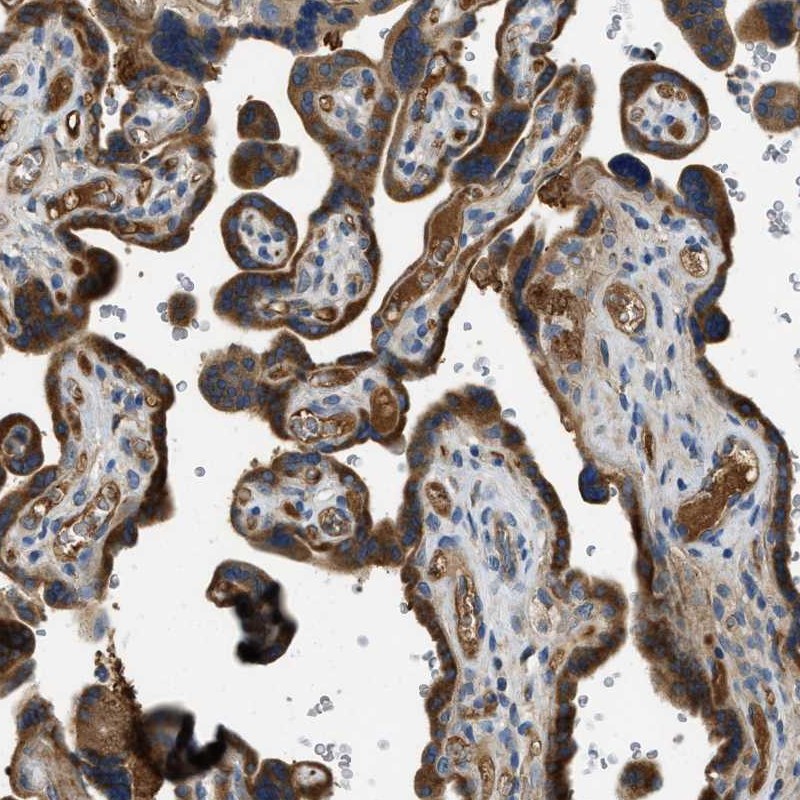

Immunohistochemical staining of human placenta shows strong cytoplasmic positivity in Trophoblasts.